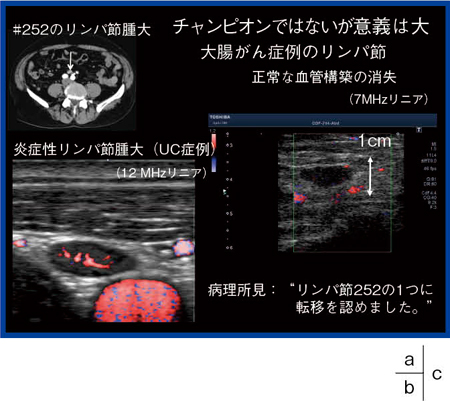

【症例7】大腸がん(炎症性リンパ節腫大)(図8)

例えば,他の症例で潰瘍性大腸がんの炎症性リンパ節腫大をDMIで見ると,リンパ節腫大から分岐するきれいな血管網が見える(図8b)。ところが,症例7のリンパ節腫大は正常な血管構築が消失し,複数の箇所から血管を引っ張ってきていることがわかる(図8c)。非造影で転移と判断し,病理所見でも♯252のリンパ節の1つに転移を認めた。これまでは非常に小さなリンパ節に対して,血管構築を正確に把握することは困難であったが,DMIによってそれが可能になってきた。

図8 症例7:大腸がん

a:CT画像

b:炎症性リンパ節腫大のDMI(12MHzリニア)

c:大腸がんのリンパ節転移のDMI(7MHzリニア)